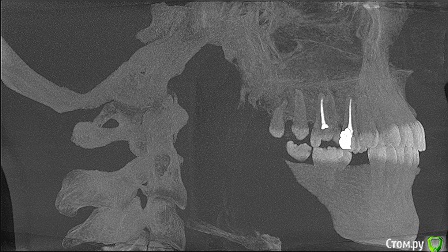

marilinka Опубликовано 4 июня, 2015 Поделиться Опубликовано 4 июня, 2015 Добрый вечер, уважаемые стоматологи!На данный момент верхняя челюсть 1 зуб, 16 под удаление......хотелось бы имплантировать, но очень боюсь, что близко к гайморовой пазухе.....в данном случае, а именно в верхней челюсти, не обойтись без синуслифтинга?И как лучше его делать непосредственно при удалении или по прошествии какого то времени?Нижняя челюсть, первичная адентия(надеюсь правильно выразилась)двух пятерок, зубов там нет даже не помню сколько лет, но лет 15-17 точно, была у 2 хирургов и оба говорят, что в местах отсутствующих зубов очень большие промежутки, то есть для 1 зуба много места, а для 2 мало.Мне бы самой очень хотелось восстановить на данный момент нижний ряд, т.к. состояние рядом находящихся зубов меня очень беспокоит. Насколько вообще возможна там имплантация, хватит ли костной ткани, возможно ли с помощью ортодонта чуть-чуть сдвинуть зубки, чтобы был 1 полноценный зуб, а не полтора? Какое время эта процедура займет?Еще 1 хирург сказал, что по моей челюсти вообще плачет ортодонт, что все у меня криво, челюсти разные и верхняя челюсть выпирает, что все это нужно исправлять....честно первый раз такое услышала...Какие варианты-схемы имплантации возможны в моем случае?Очень надеюсь на советы. На врачей в своем городе к сожалению не могу понадеяться, была у 2 и об обоих не сложилось впечатление достаточно компетентных врачей в этом вопросе. Ссылка на комментарий

marilinka Опубликовано 5 июня, 2015 Автор Поделиться Опубликовано 5 июня, 2015 а вот так...поизвращалась как могла Ссылка на комментарий